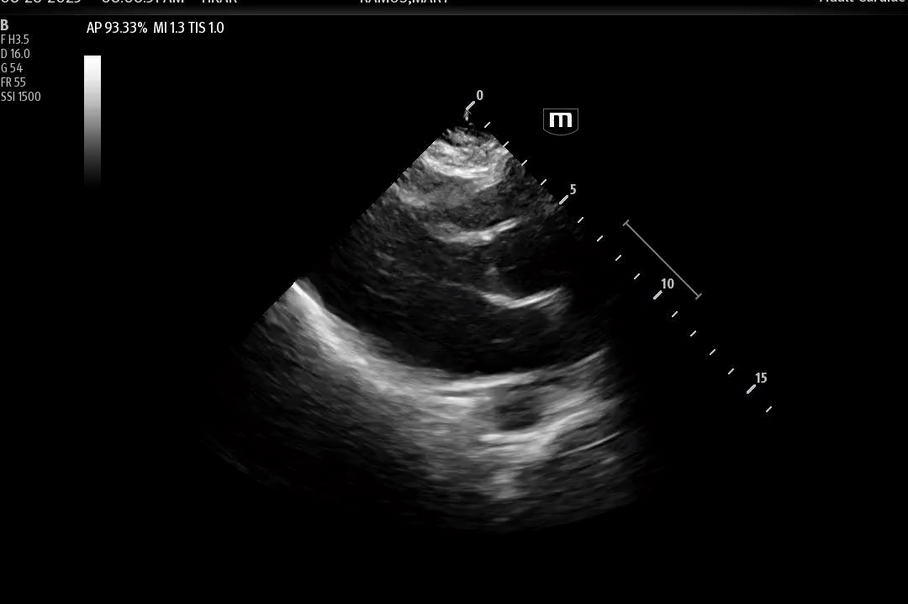

Bedside POCUS

• There was inferolateral wall motion abnormality, basal hypercontractility, apical ballooning

• No pericardial effusion.

Here are the POCUS images:

• This POCUS finding may also be described as systolic apical ballooning of the LV with hyperkinesis of the basal walls. Of note, there are also less common regional wall motion abnormalities seen.